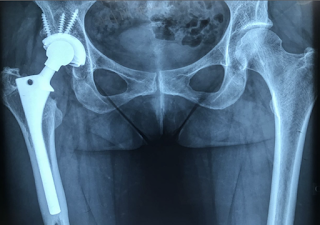

Existem diversos tipos de próteses de quadril, sendo que a mais utilizada é a prótese total de quadril que possui um metal recoberto internamente de plástico ou cerâmica. Na cirurgia é feita uma substituição da articulação doente e disfuncional para uma articulação nova que devolve mobilidade, funcionalidade e elimina as dores do paciente.